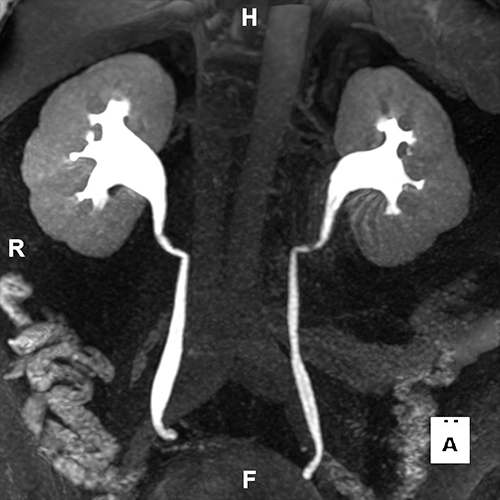

Our Urology Service utilizes MR Urogram with advanced 3D imaging technology to provide three-dimensional reconstructions of the urinary tract. By employing MRI, we are able to harness the power of T2-weighted imaging, which is particularly effective for the clear visualization of fluid-filled structures within the urinary system. This technique ensures that areas such as the bladder, ureters, and kidneys are depicted with high clarity, aiding in the comprehensive assessment of these critical structures.

To further enhance the diagnostic capability of our imaging, we may also include post-contrast sequences. These sequences delineate the urothelium, the layer of tissue lining the urinary tract, and for the detection of any lesions or abnormalities. This dual approach, combining T2-weighted and post-contrast imaging, may provide a thorough evaluation of the urinary tract's health, highlighting both the normal anatomical features and any potential issues that may require closer examination or intervention.